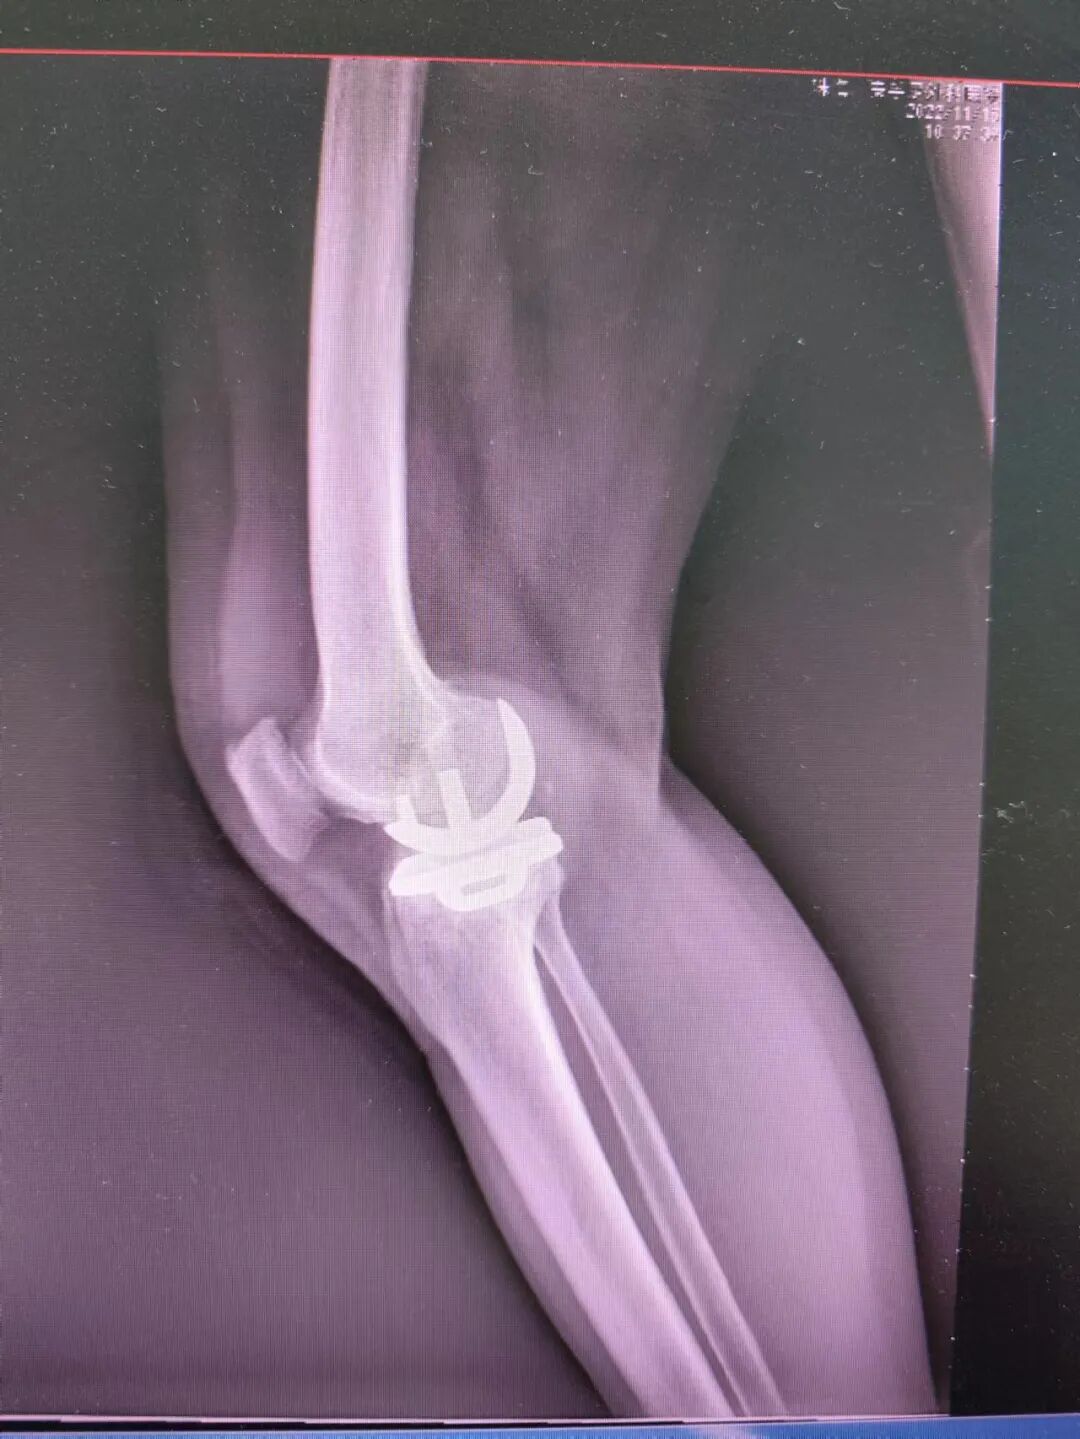

结合患者病史、查体及影像学资料,经科内会诊后决定给吴女士行人工单髁关节置换术,术中所见:

术后第二天扶助行器下地行走。

术后DR。